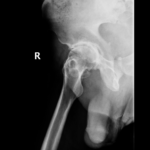

Diagnosis

Diagnosis is made by evaluating medical history, physical examination and X-rays.